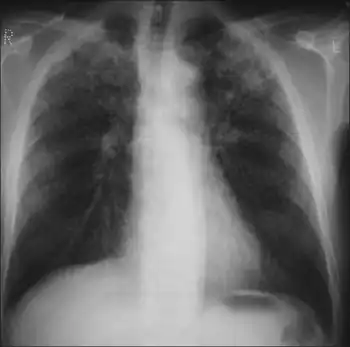

- Chest X-ray may show a characteristic patchy, subpleural, bibasilar interstitial infiltrates or small cystic radiolucencies called honeycombing, particularly in advanced disease.[16][17][18][19]